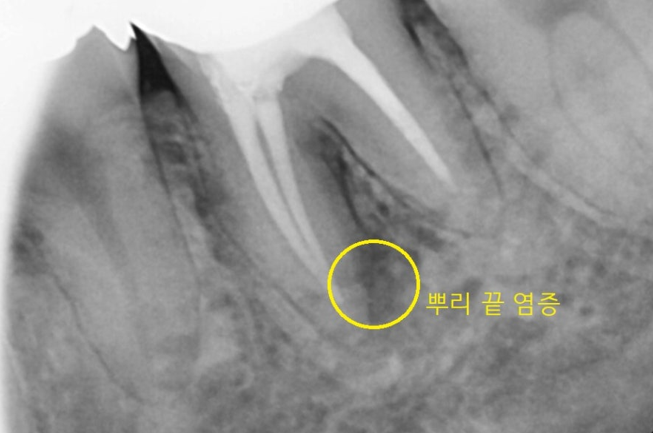

두 번째 부위

왼쪽 아래입니다.

신경치료도 되어있고

뿌리 끝에 염증도 있네요..

환자분께서는 아프진 않지만

불편하다고 해주셨어요

물집처럼 뭐가 한번씩 올라오기도 하고

치아도 흔들린다고요.

단순 염증만 있으면 재신경치료로

살려볼 수 있겠지만

231104

치근 분지 부위

그러니까 치아 뿌리가 나눠지는 부분이

그 부위가 까맣죠..?

뼈가 녹아서 까맣게 보입니다.

문제는 이 가운데 부분은

치료하기가 어렵습니다.

갈라져있어서 어떤 기구를 사용해도

염증 제거가 잘 안되는데요.

이대로 그냥 쓰시는 것은

뼈를 계속 녹일 수 있고

앞 뒤 치아로 염증이 퍼질 수 있어서

발치 필요함을 상담해드렸습니다.